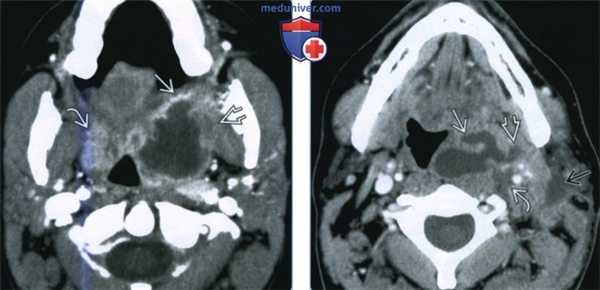

(Слева) При КТ с КУ в аксиальной проекции определяется большой МА с содержимым пониженной плотности. Распространения в окологлоточное пространство за пределы капсулы миндалины нет. Левая миндалина увеличена и накапливает контраст, но признаков абсцедирования нет. Обратите внимание на сопутствующий выпот в заглоточном пространстве.

(Справа) При КТ с КУ в аксиальной проекции определяются миндаликовые абсцессы с обеих сторон, левый по размерам больше правого. Абсцессы сдавливают оба окологлоточных пространства, но распространения воспалительного процесса на окружающие структуры нет. Просвет дыхательных путей сужен и имеет щелевидную форму.

2. КТ при миндаликовом и паратонзиллярном абсцессе:

• КТ с КУ:

о Миндаликовый абсцесс: увеличенная небная миндалина(ы) с центральным участком пониженной плотности и периферическим кольцом накопления контраста:

- По данным КТ с контрастированием дифференцировать отек миндалины от сформированного абсцесса сложно

- Очень важно дифференцировать МА от простого воспаления миндалины, поскольку лечение может различаться

- Воспалительная исчерченность окружающих клетчаточных пространств

о Паратонзиллярый абсцесс: миндаликовый абсцесс распространяется в окружающие пространства:

- Окологлоточное, жевательное, поднижнечелюстное пространства

о У подростков и у взрослых часто сочетается с выраженной двусторонней реактивной шейной аденопатией

(Слева) При КТ с КУ в аксиальной проекции визуализируется левосторонний МА и ПТА, распространяющийся через капсулу миндалины в заднее щечное пространство и медиальную крыловидную мышцу жевательного пространства. Отмечается накопление контраста в правой воспаленной миндалине, но данных за абсцедирование здесь нет.

(Справа) При КТ с КУ в аксиальной проекции наблюдается осложненный левосторонний МА больших размеров. Инфекционный процесс распространился в сонное пространство В, в переднелатеральном направлении в верхнее поднижнечелюстное пространство, в латеральном направлении в нижние отделы пространства околоушной железы.

КТ с контрастированием: левосторонний паратонзиллярный абсцесс. Образование имеет гипоинтенсивный центр, окруженный усиленной стенкой. Отек левой нёбной миндалины и слизистой глотки на стороне поражения вызывает асимметричное сужение глотки. Рот остается открытым в связи с болевым синдромом.

КТ с контрастированием (реконструкция во фронтальной плоскости): левосторонний паратонзиллярный абсцесс. Выявляется перифокальный отек и повышенная плотность слизистой, а также асимметричное сужение ротоглотки, распространяющееся в дистальном направлении слева от мягкого нёба. В абсцессе наблюдается типичное периферическое усиление с гипоинтенсивной полостью в центре.